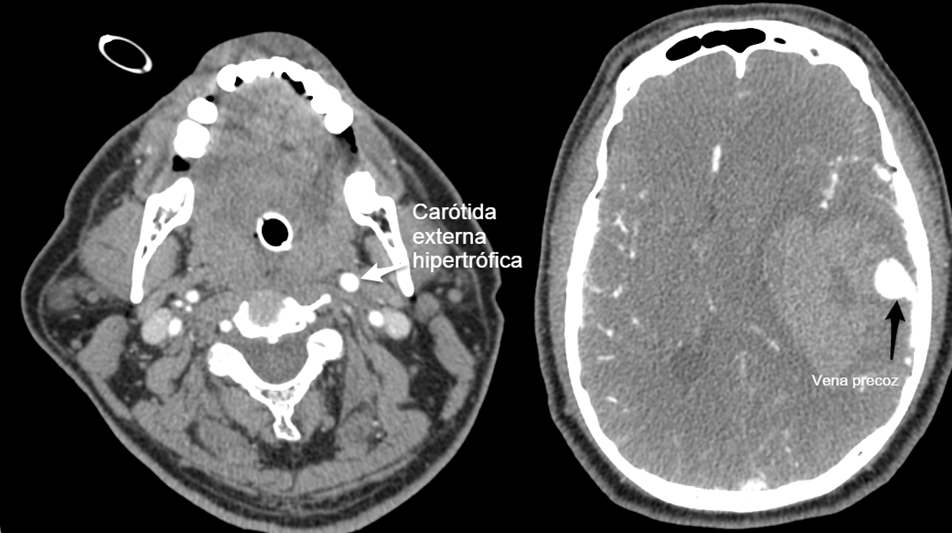

En TC realizado en la urgencia se observa hematoma intraparenquimatoso temporal izquierdo que desplaza 16 mm las estructuras de línea media y produce herniación uncal izquierda (imagen 1).

Se procede a realizar angioTC de troncos supraaórticos observando un drenaje venoso precoz de venas corticales temporales izquierdas y aumento de calibre de la arteria carótida externa izquierda, hallazgos compatibles con posible fístula dural (imagen 2).